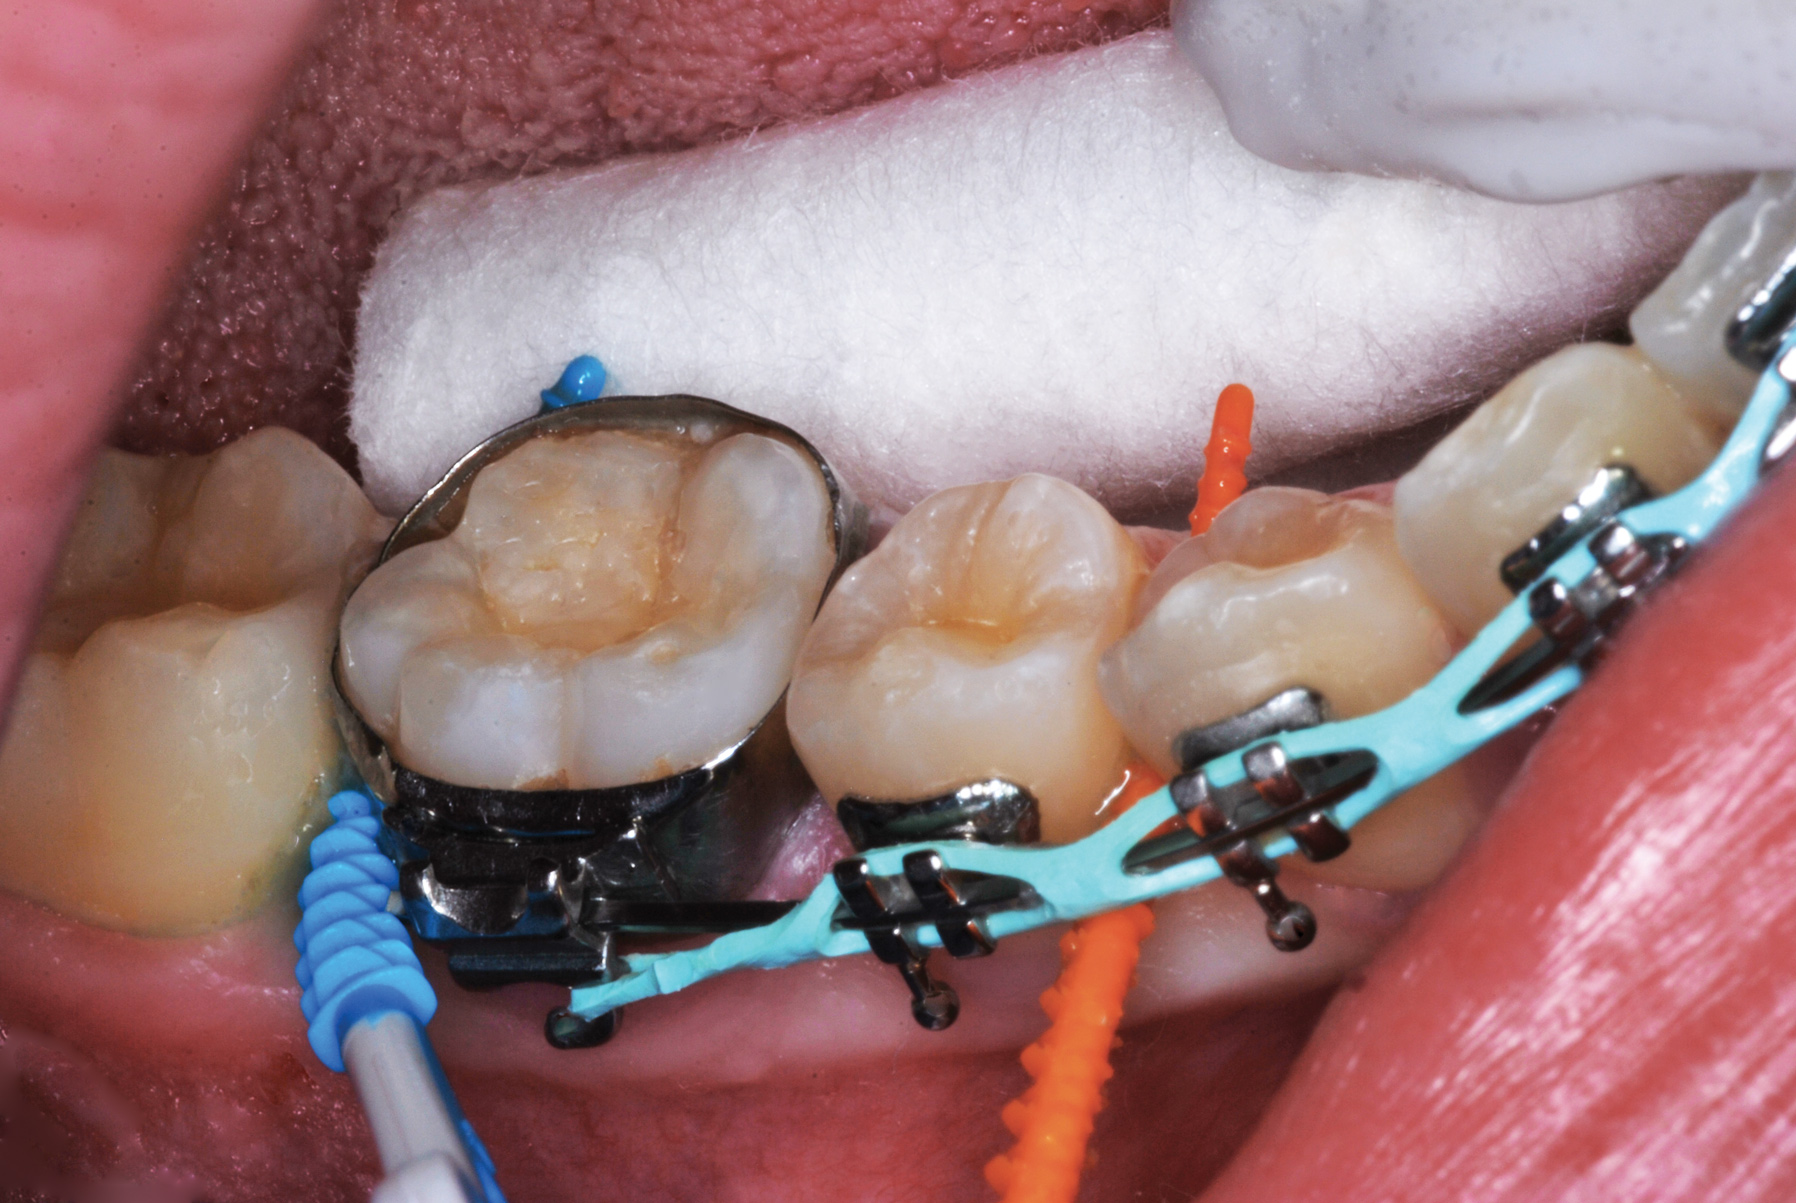

Figure 7 illustrates the use of thicker picks in premolar interproximal sites. Additionally, multiple picks can be used in one quadrant or in one proximal site with good isolation to maximize fluid saturation (Figure 9), which the authors have found to be an excellent time-saving strategy. Preventive or interceptive applications of SDF may also be effectively used in interproximal sites in orthodontic patients (Figure 10).

Fig 10. Interproximal sites in orthodontic patients can also benefit from preventive or interceptive SDF applications.

Figure 10